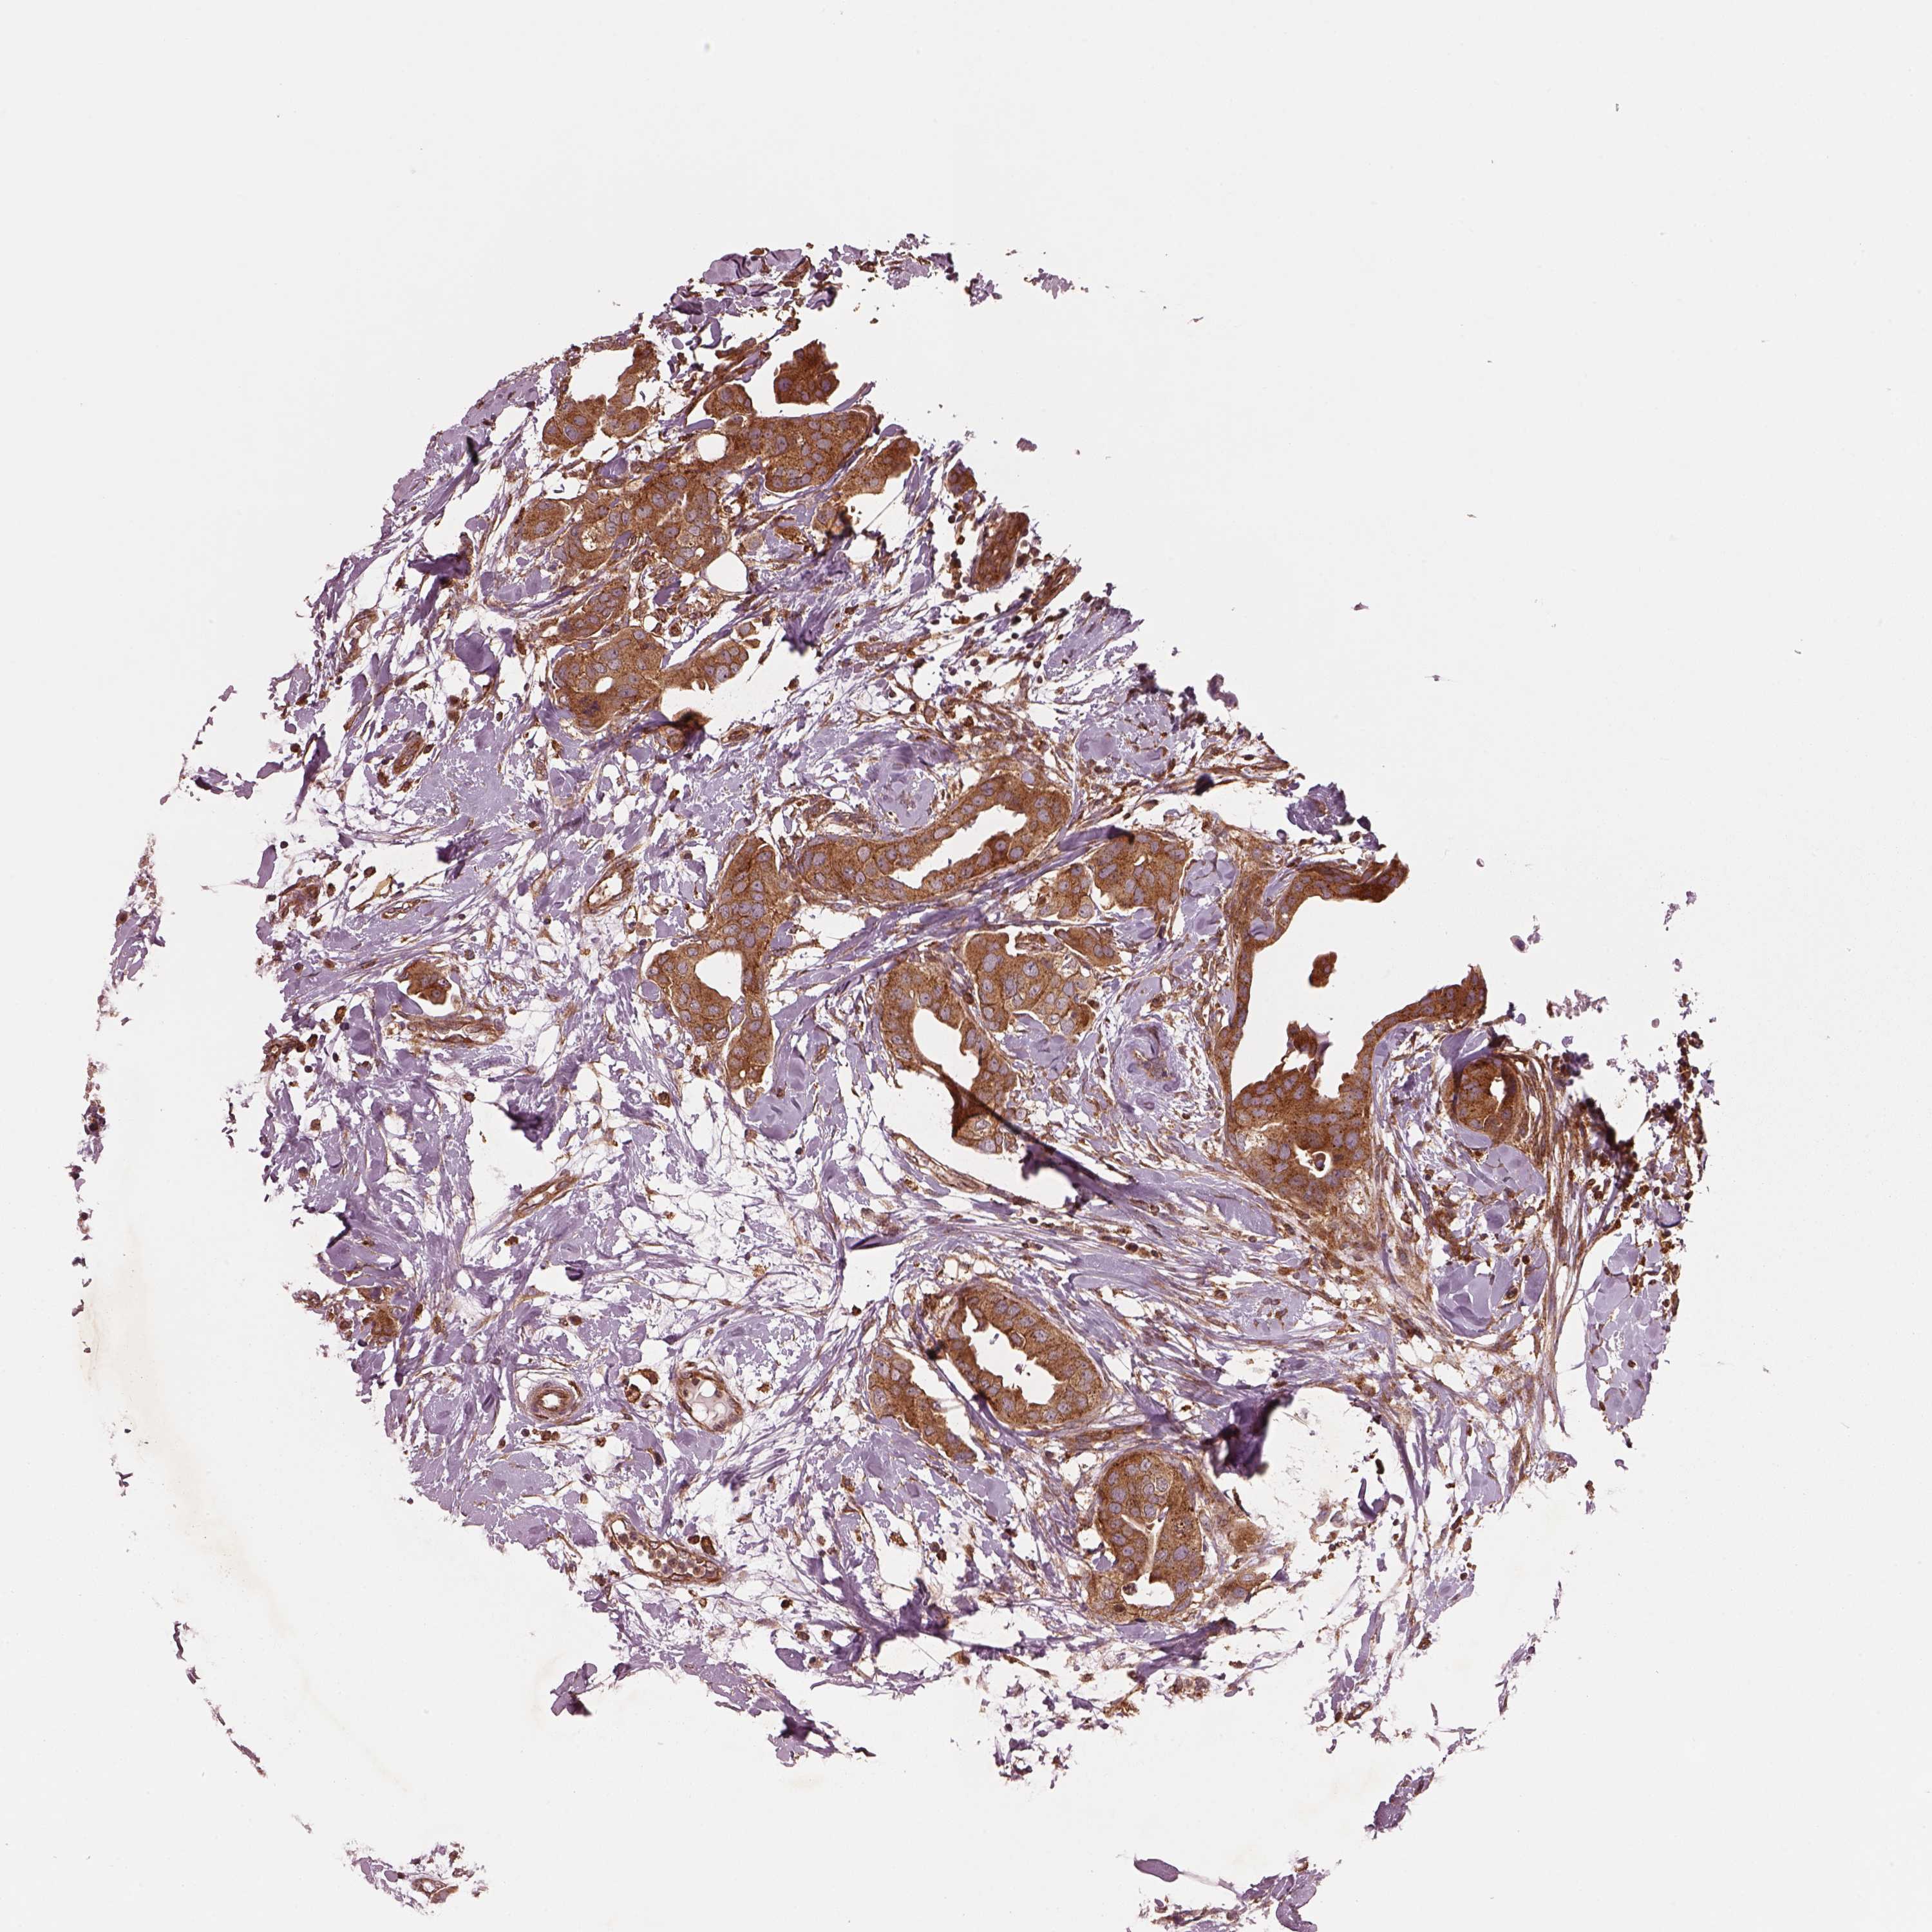

CANCER BREAST CANCER Show tissue menu

BRCA TCGA BRCA VALIDATION PROTEIN EXPRESSION